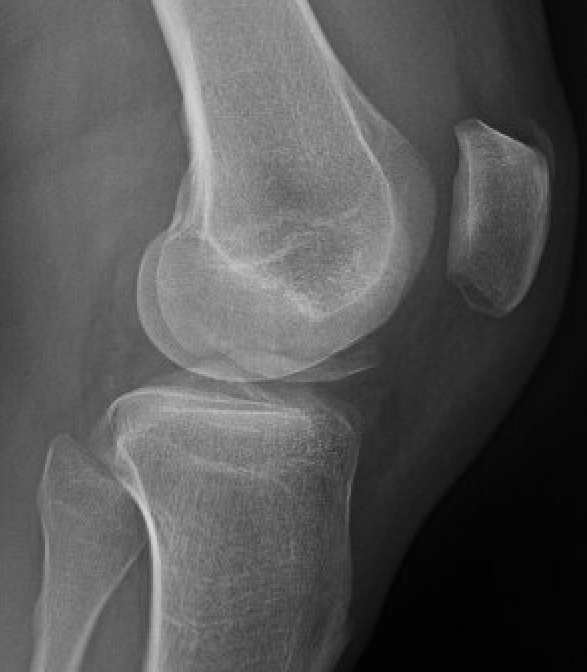

Xray

Look for osteochondral fractures

- skyline xray: suprapatella pouch

- lateral xray: notch

- AP xray: gutters

Loose body in notch with donor site from patella

Loose body in lateral gutter